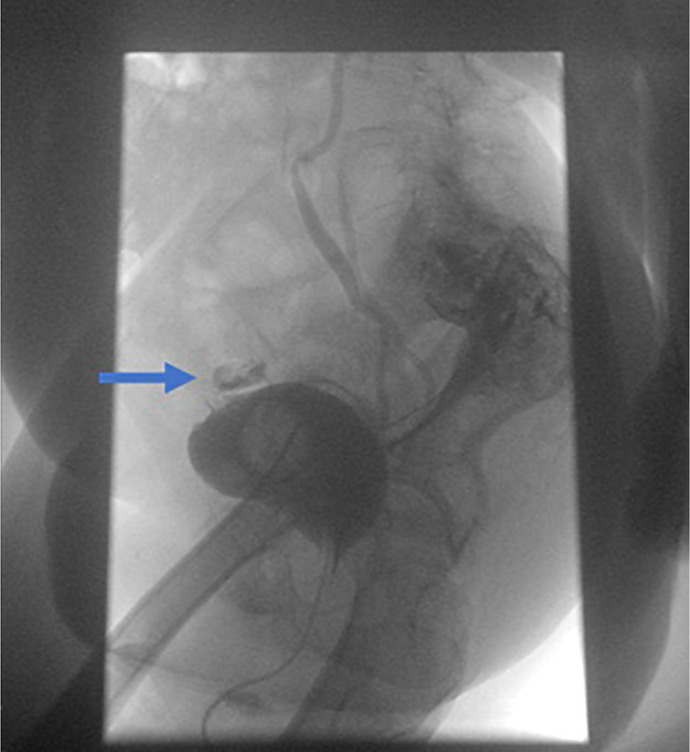

Case presentation: Although VPF mainly occurs as an early postoperative complication of gynecological surgery, we report a case of a 71-year-old female patient who presented with ascites, pseudo-renal failure, and peritonitis caused by a VPF as a delayed complication of radiotherapy.

Conclusion: In this case report, we discuss treatment strategies based on previously published case studies and our experience. We provide a diagnostic overview of commonly available imaging techniques, such as computed tomography scans and magnetic resonance imagings. Despite their widespread use, these imaging modalities have not led to any shift in the diagnostic process, with the definitive diagnosis being confirmed only by retrograde cystography.